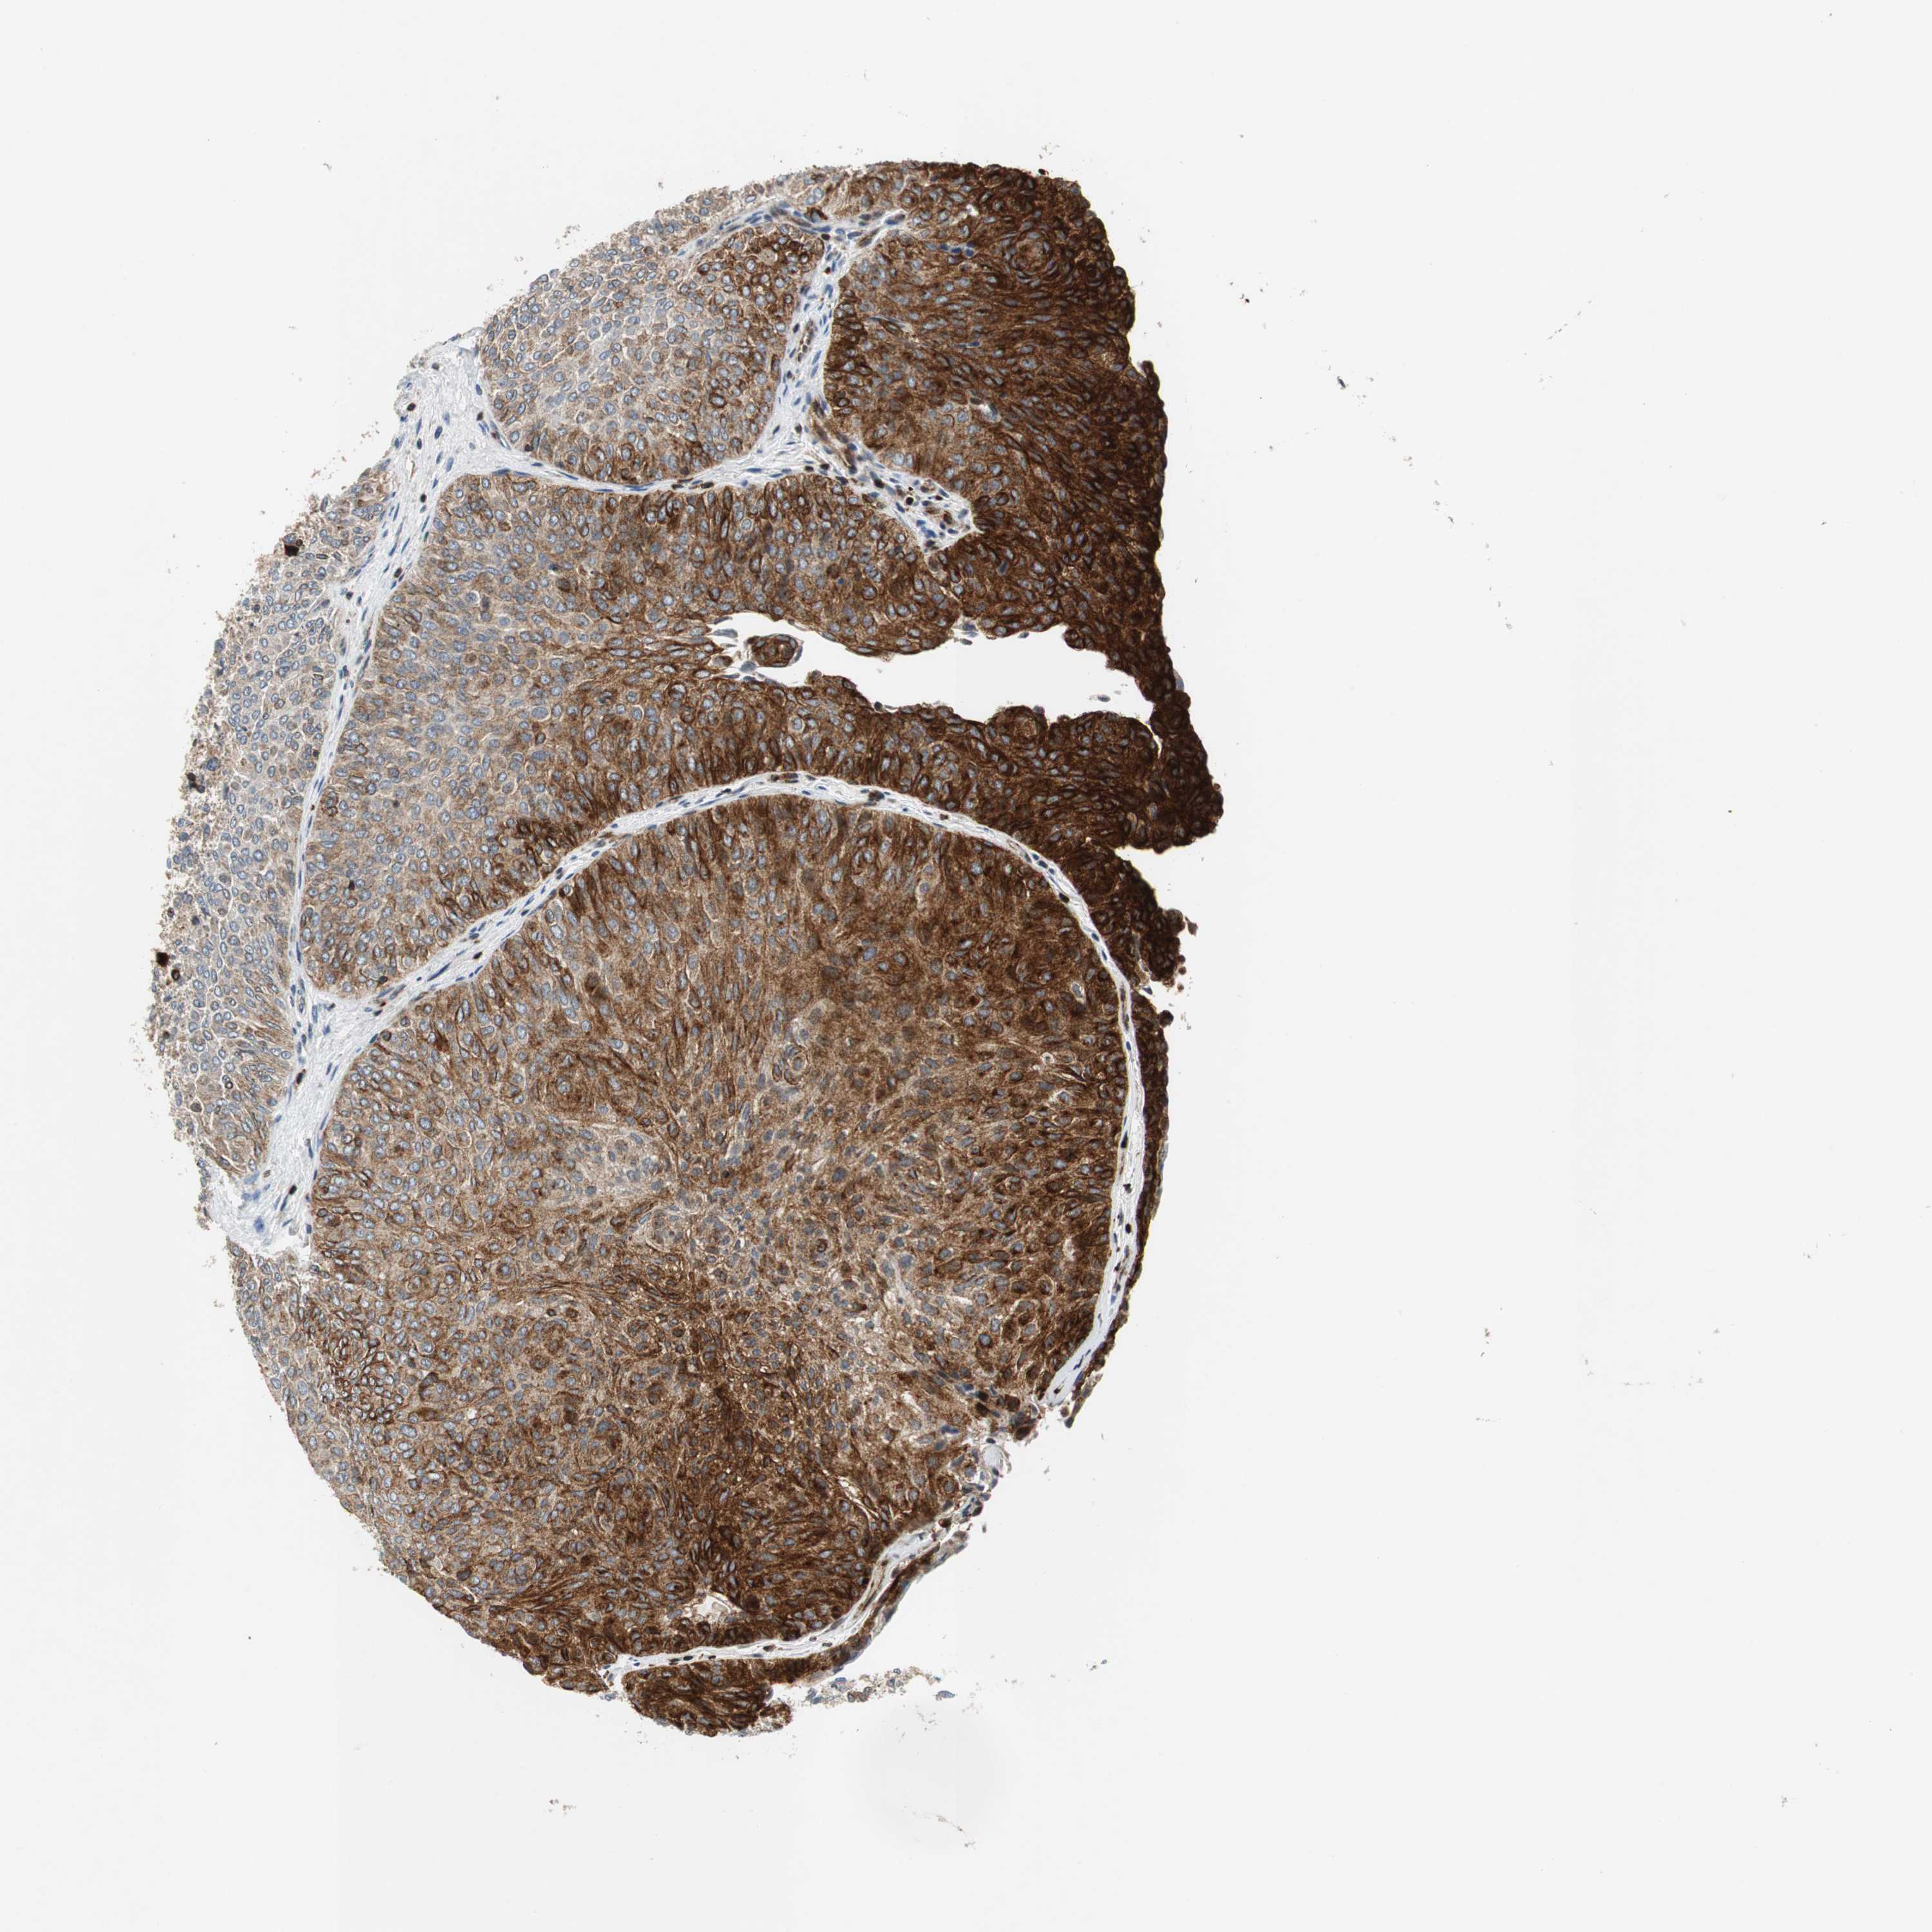

UROTHELIAL CANCER - Protein expressioni

A mouse-over function shows sample information and annotation data. Click on an image to view it in a full screen mode. Samples can be filtered based on level of antibody staining by selecting one or several of the following categories: high, medium, low and not detected. The assay and annotation is described here.

Note that samples used for immunohistochemistry by the Human Protein Atlas do not correspond to samples in the TCGA dataset.

Antibody stainingi

Antibody staining in the annotated cell types in the current human tissue is reported as not detected, low, medium, or high, based on conventional immunohistochemistry profiling in selected tissues. This score is based on the combination of the staining intensity and fraction of stained cells.

Each image is clickable and will lead to virtual microscopy that enables deeper exploration of all samples and also displays staining intensity scores, fraction scores and subcellular localization as well as patient and tissue information for each sample.

HPA039247

HPA043684

HPA063394

CAB004621

CAB005887

Staining

High

Medium

Low

Not detected

Intensity

Strong

Moderate

Weak

Negative

Quantity

>75%

75%-25%

<25%

None

Location

Nuclear

Cytoplasmic/membranous

Cytoplasmic/membranous,nuclear

Urothelial carcinoma, High grade

Urothelial carcinoma, Low grade